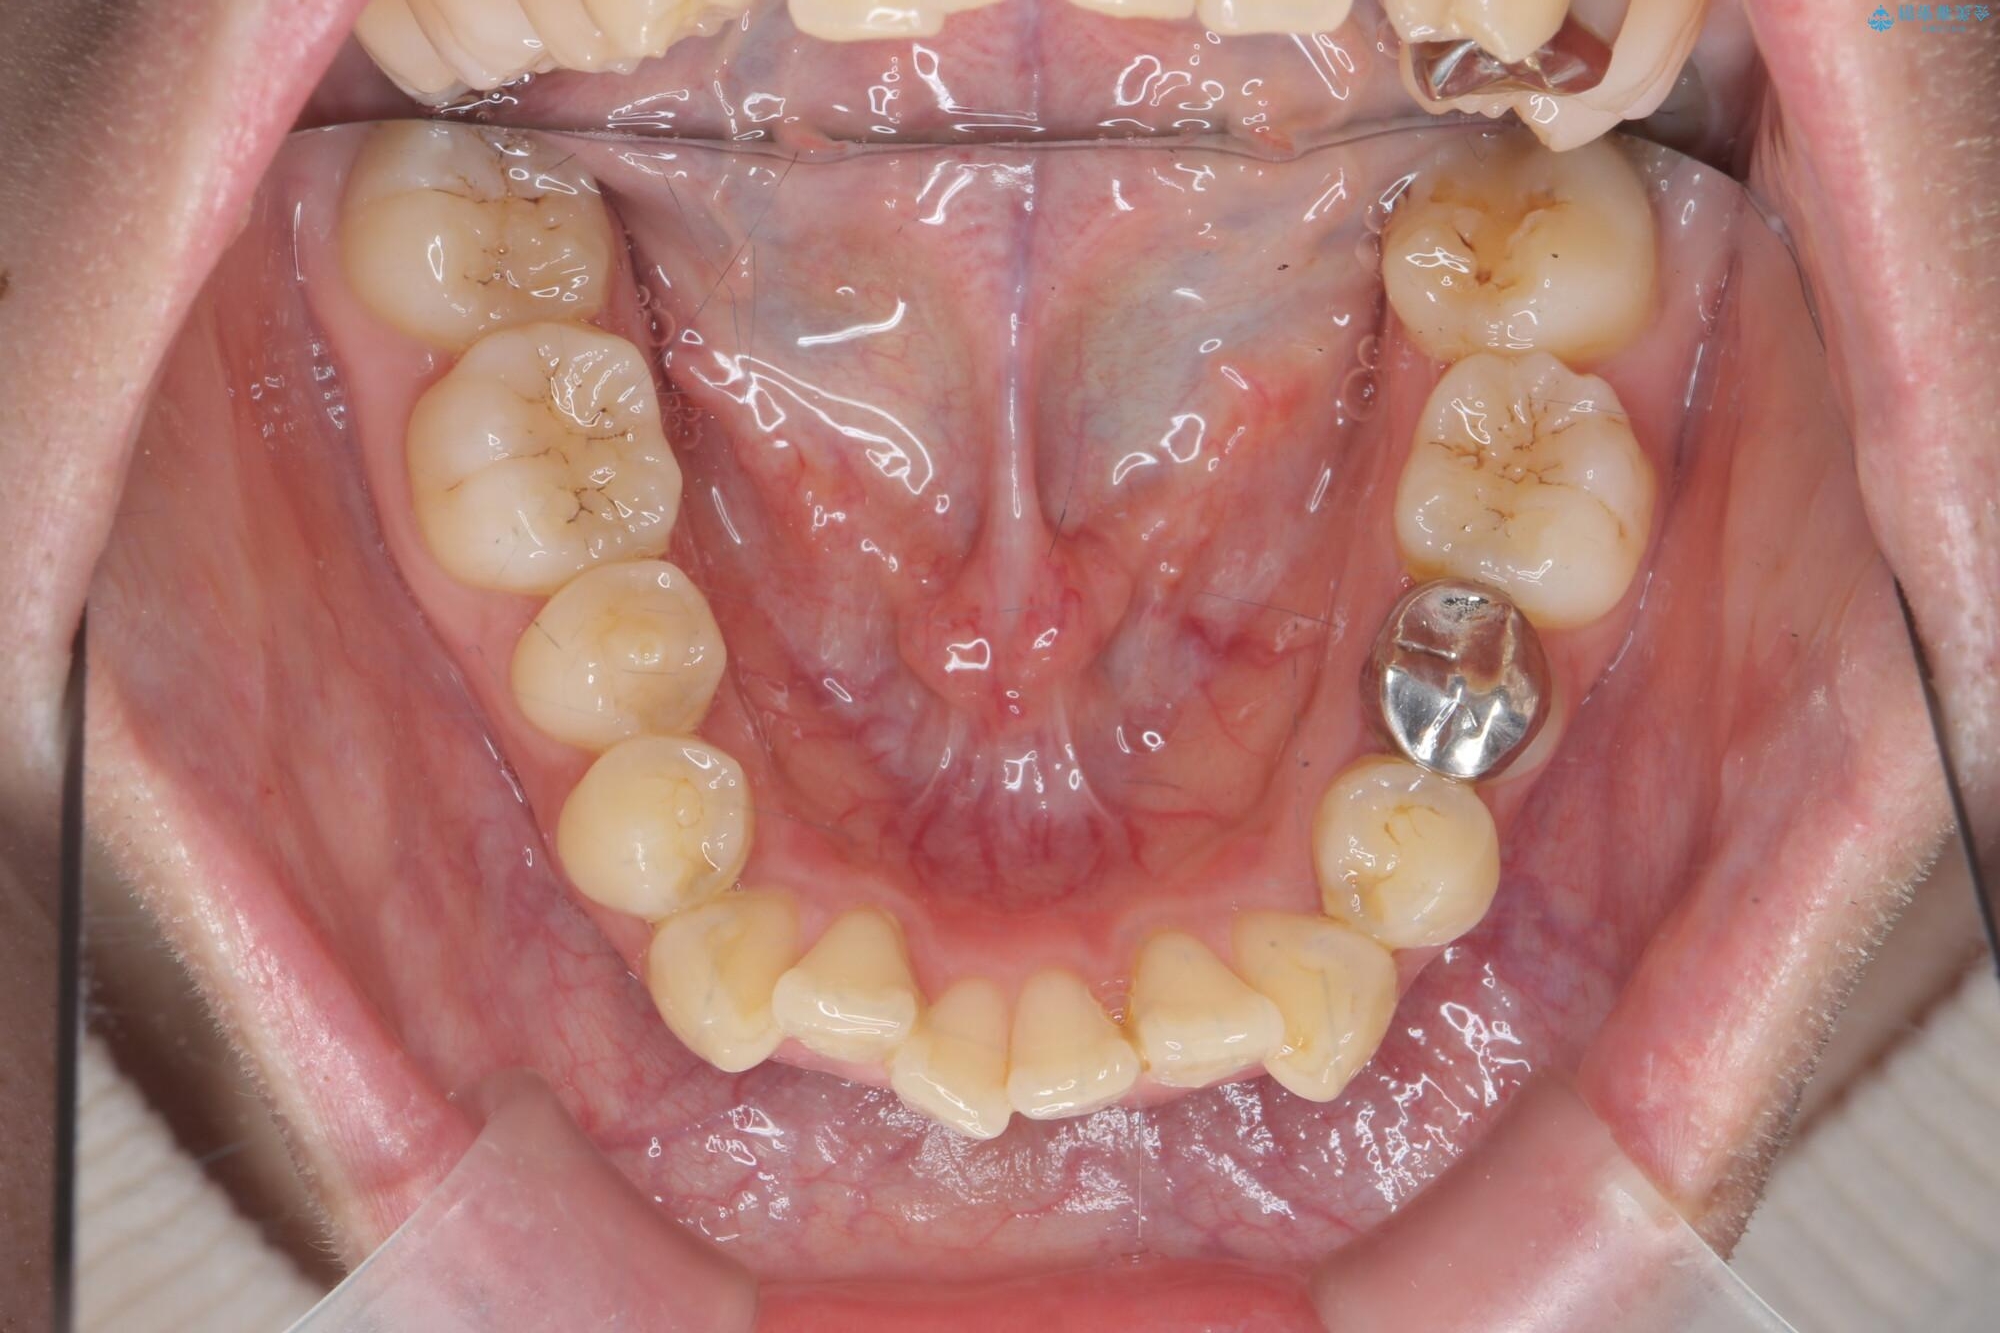

治療前

気になる犬歯のガタつきをマウスピース矯正で改善 治療前画像 気になる犬歯のガタつきをマウスピース矯正で改善 治療前画像 気になる犬歯のガタつきをマウスピース矯正で改善 治療前画像 気になる犬歯のガタつきをマウスピース矯正で改善 治療前画像